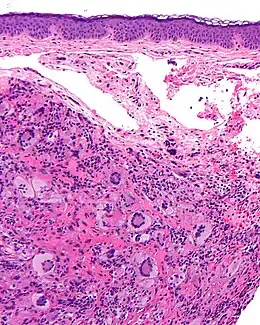

- Aspect histologique : La nature de l'infiltrat diffère selon l'âge de la lésion. L'aspect inflammatoire est moins visible (avec cytoplasme homogène et éosinophilique ou amphophilique) dans les lésions récentes. Ensuite, la part de l’infiltrat inflammatoire augmente et le cytoplasme des histiocytes est vacuolé et xanthomateux. Quand la lésion guérit elle est caractérisée par des fibroblastes et une fibrose. Les cellules géantes sont plus rares dans les lésions précoces et vieilles[14]. Des noyaux atypiques et des figures mitotiques sont parfois visibles [15]. L’activité mitotique est plus visible dans les lésions jeunes précoces[14].

Histologie

Les xanthogranulomes contiennent dans un premier temps des histiocytes non lipidiques, sans cellules de langerhans. Ensuite, des cellules inflammatoires (dont des histiocytes spumeux) apparaissent, de plus en plus nombreuses avec la maturation de la tumeur. Des cellules géantes de Touton aux noyaux arrangés en couronne, sont typiques, avec parfois d'autres cellules géantes, « endothéliales »[20].

La coupe histologique (grossissement : × 40) montre un infiltrat dermique (dense et bien limité) composé d'histiocytes, de cellules géantes de Touton, et parfois de cellules mastocytaires, et d’un infiltrat inflammatoire lymphocytaire (lymphocytes, éosinophiles, neutrophiles).

L'infiltration affecte le derme papillaire et parfois réticulaire ou le niveau des tissus sous-cutanés, du fascia et des muscles.

Le derme peut être très aminci par l'infiltrat et alors s'ulcérer.